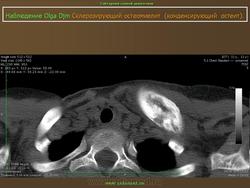

Склерозирующий остеомиелит из ключицы впервые был описан как заболевание лица в 1974 году. Существует боли и часто локализуется опухоль из медиальной трети ключицы, с повышенной плотностью радио.Sternoclavicular совместных, как правило, никогда не занимался. Он также известен как асептический расширения остеосклероз из медиального конца ключицы.

Исследования должны включать СКС, СОЭ, рентген, МРТ, реакция Манту и крови серологические, чтобы исключить инфекцию. Биопсия является обязательным для получения материала для гистологических и бактериологических культуры.

Множественные мелкие и крупные (до 10 мм) очаги остеосклероза округлой или овальной формы, расположенные в эпифизах трубчатых костей, а также в других костях, за исключением ключицы.